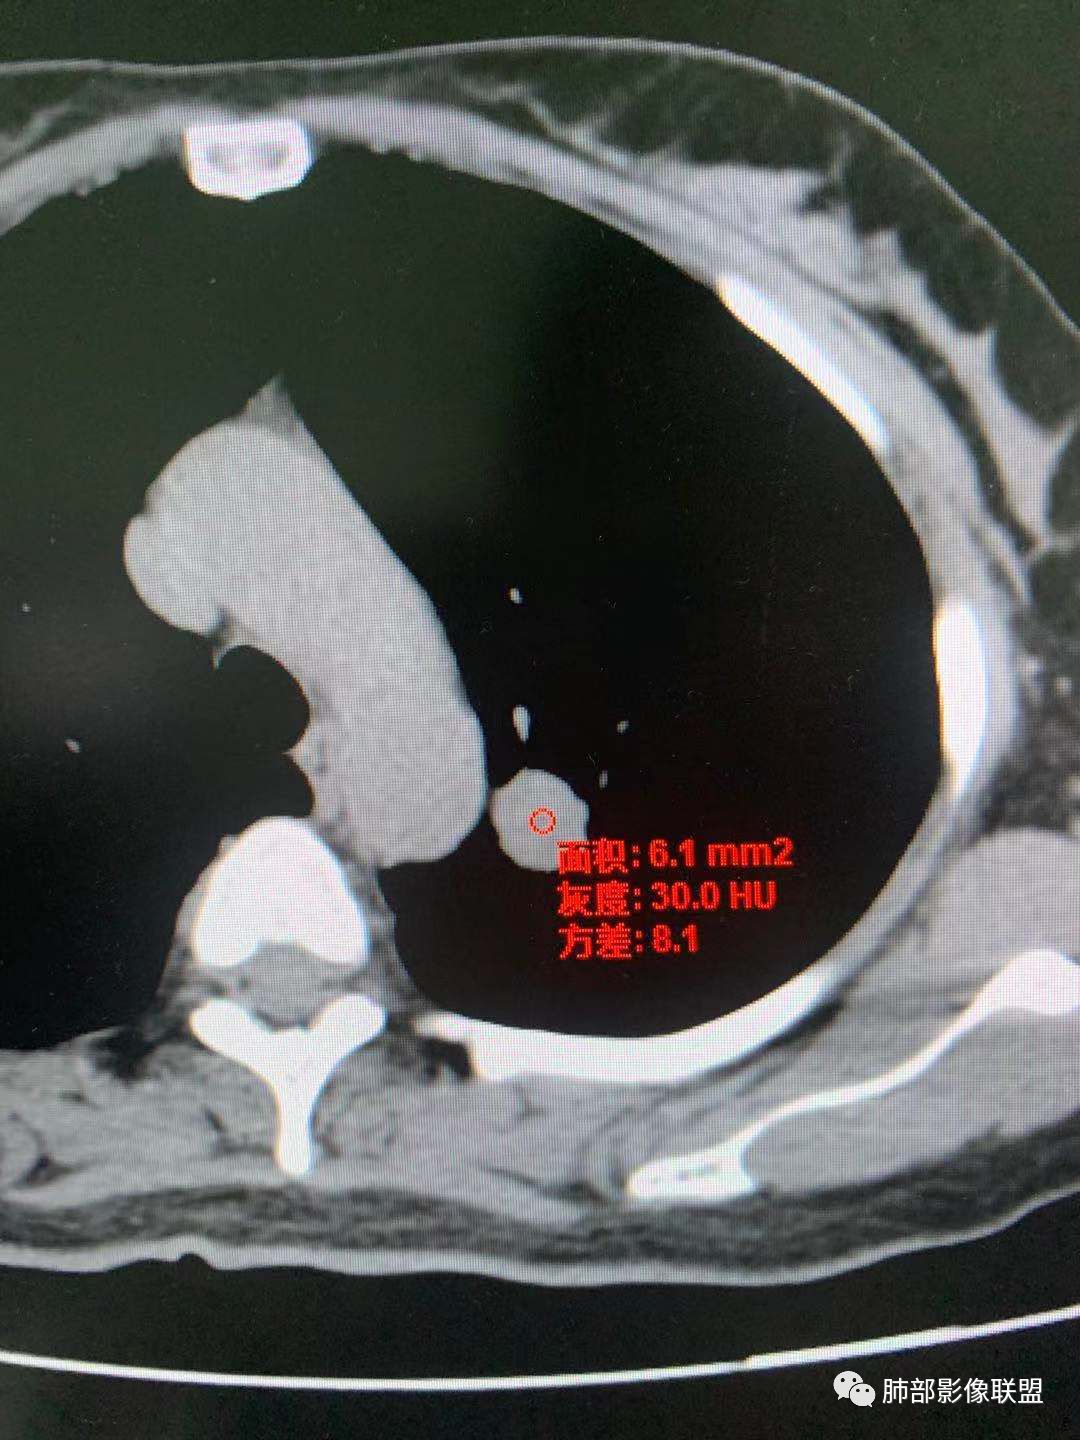

有棘状突起,强化渐进性,强化了四十左右

CT值30HU;增强后:41/76HU

强化幅度:46HU